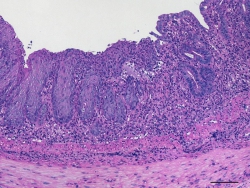

FOTO 2: Die Infiltration von Immunzellen in die Schleimhaut des Dickdarms einer Maus wurde nach chemisch-induzierter Kolitis mittels Hematoxylin und Eosin Färbung nachgewiesen.

Foto: Dr. Anja A. Kühl